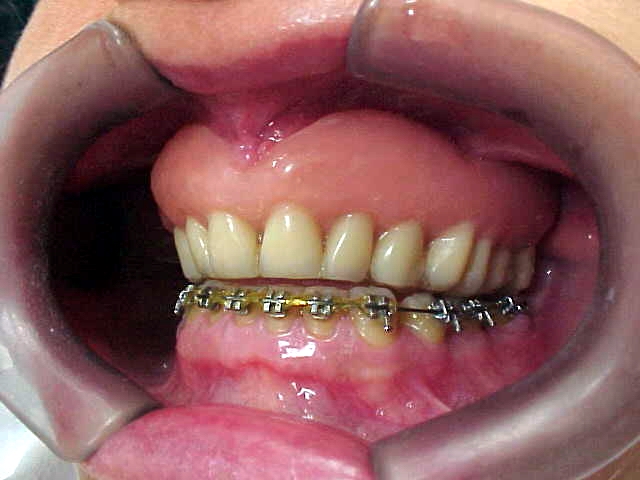

Aparelho ortodôntico instalado

Aumento posterior para facilitar mecânica ortodôntica no arco inferior